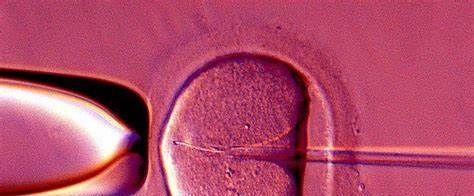

网友提问:高龄做试管婴儿试管婴儿成功率真的有那么高吗?高龄做试管婴儿试管婴儿成功率是多少呢,我们经常被各种的广告夸大其词的宣传,我们今天一起通过数据和案例来看看成功率到底有多少:

高龄做试管婴儿试管婴儿成功率只有百分之4 ,不是吓唬大家,确实是实情,上面是一张各年龄段做试管婴儿试管婴儿成功率的的统计图,不难看出每个年龄段能做试管婴儿试管婴儿的成功率是根据年纪出现下降的趋势,在30岁以下的成功率可以达到百分之70,而到了30-35岁只有百分之65,35-38岁便只有了60%,越往下越少,最后在44岁以上高龄的时候试管婴儿的称功率只有了百分之5以下,也可以说只有百分之4。